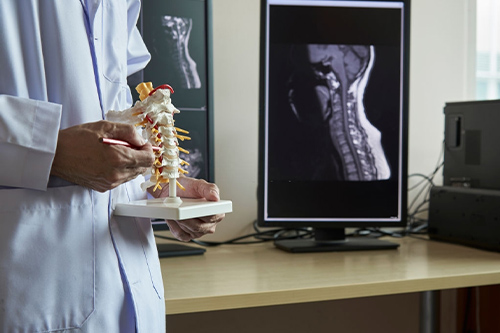

En nuestra clínica de neurocirugía te ofrecemos los mejores y más novedosos tratamientos para la atención de cualquier enfermedad que afecte a tu sistema nervioso, así mismo, para lesiones y enfermedades de la columna.

Contamos con tecnología de vanguardia para ofrecerte técnicas mínimamente invasivas, si te interesa recibir una consulta de valoración en la mejor clínica de neurocirugía de la CDMX, llámanos, te atenderemos con gusto.

Si quieres recibir atención médica especializada en la mejor clínica de neurología de CDMX, somos tu mejor opción, agenda tu cita o si lo prefieres visitanos en Star Médica Tlalnepantla y Hospital Boutique Riobamba.

En nuestra clínica de neurología encontrarás al mejor Neurocirujano, el Doctor Samuel Morgado, médico especialista altamente comprometido con tu salud, cuenta con gran experiencia y constantemente se actualiza para ofrecerte tratamientos de la más alta calidad.